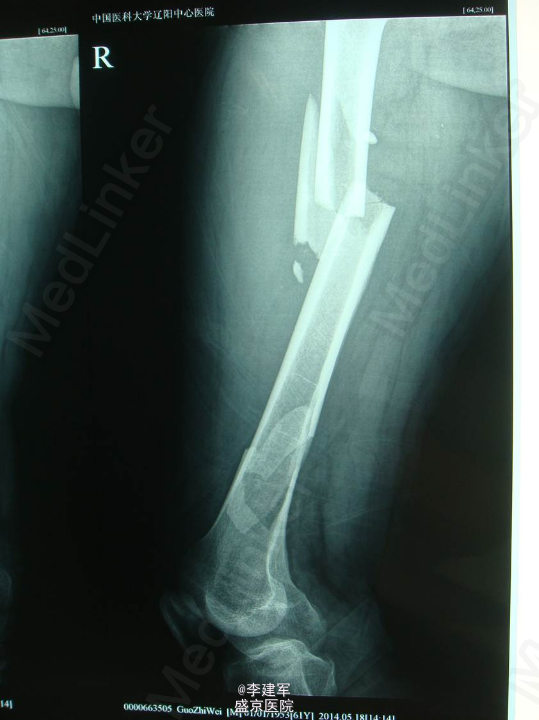

主诉:摔倒后右大腿疼痛肿胀活动受限5小时 现病史:患者家属自述骑自行车自行摔倒,摔倒后右大腿疼痛肿胀,活动受限,伤后患者昏迷约一小时,急诊送入当地医院,DR(当地医院)提示右股骨干骨折,当地医院给予患肢皮牵引固定等对症治疗。今日患者为求进一步手术治疗来我院治疗。门诊以“右股骨干骨折”为诊断收入院。患者病来一般状态可,生命体征平稳,无发热,饮食睡眠可,二便正常。

专科查体:患者平车推入病房,右下肢短缩屈曲中,右大腿疼痛,肿胀明显,可触及反常活动及骨擦感,纵向叩击痛阳性。右大腿外侧可见皮肤瘀斑,右足背动脉搏动正常,足趾活动可,皮肤感觉较健侧无明显异常。

诊断:右股骨干粉碎性骨折 患者右股骨干粉碎性骨折,拟行右股骨干骨折闭合复位内固定术。